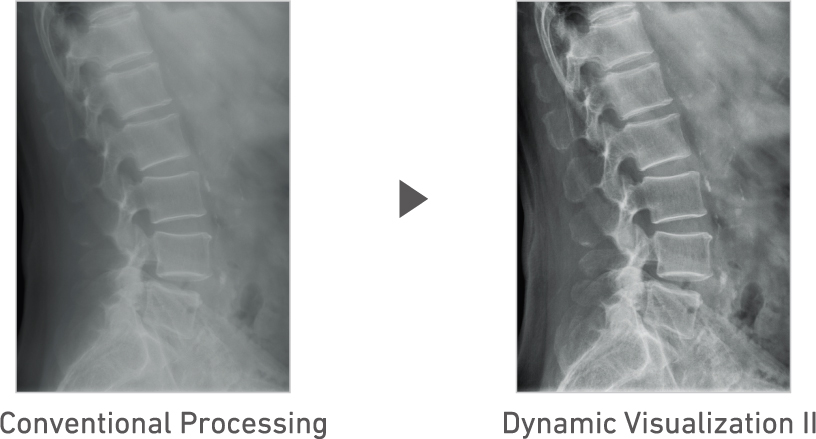

FDR D-EVO III utilizes the latest Fujifilm digital image processing technologies including Dynamic Visualization, which optimizes image display based on monitor characteristics and FNC noise suppression processing that improves image quality, automatically extracting and separating noise components in the image.

Advanced recognition algorithms automatically adjust contrast and density for individual body parts based on calculation of estimated 3D image data. (Option)